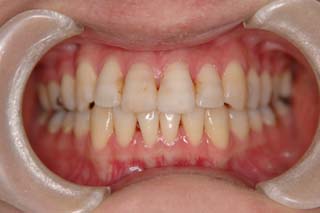

(叢生/正中変位/上右小臼歯抜歯(片顎片側抜歯)/ ハーフリンガル)

骨格的な非対称や治療前に見られた咬耗など、対処が難しい問題もありますが、前歯部被蓋、臼歯関係ともに良好です。今後、保定管理を継続する予定です。